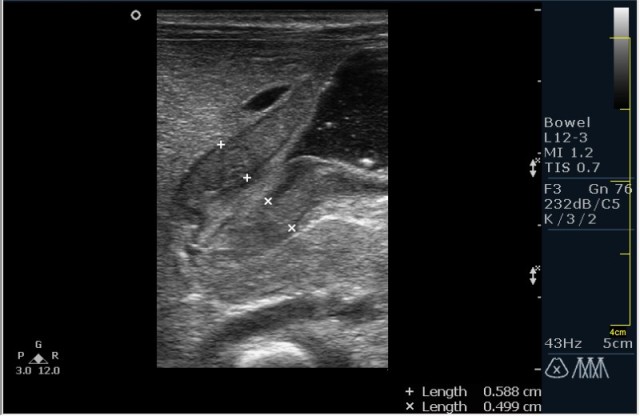

Ребёнок 1 месяц 10 дней от родy, с отсуствием прибавки в весе.

Hypertrophic pyloric stenosis.

Criteria:

1.Pyloric channel > 12 mm in length

2.Muscular layer thickness > 3-4 mm

3.Donuts sign at transverse scanning